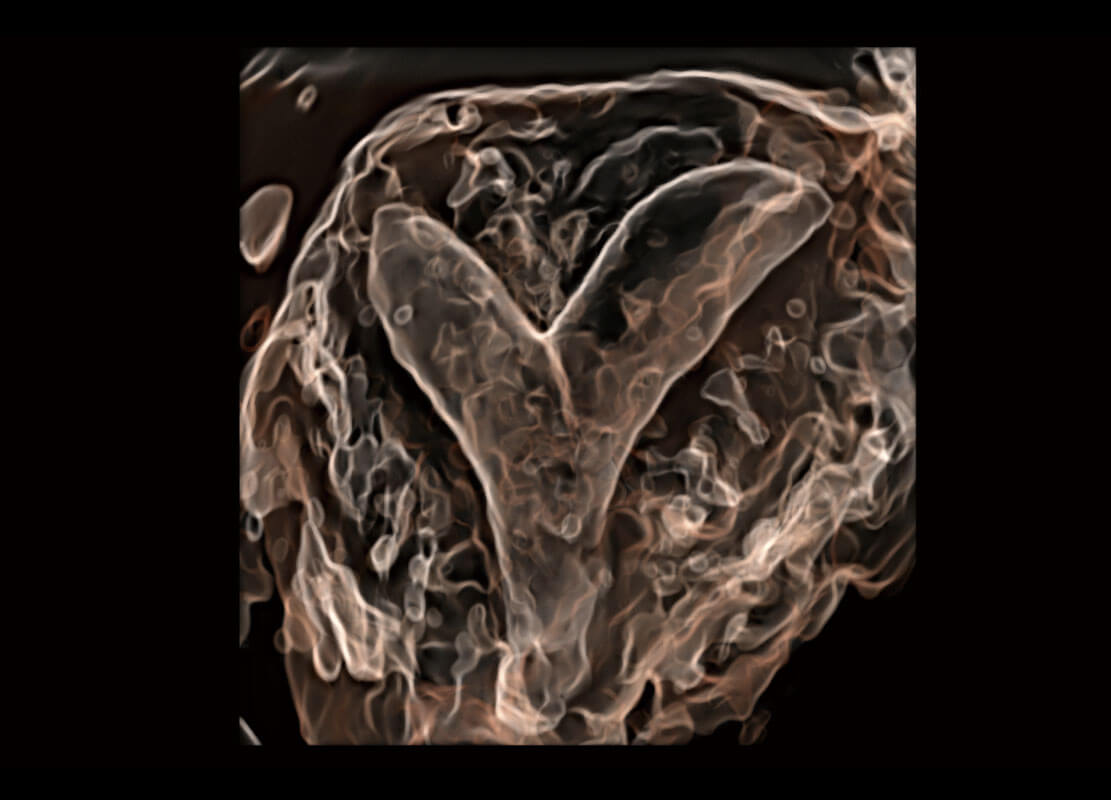

腔内三维-光影成像

光影成像-孕囊